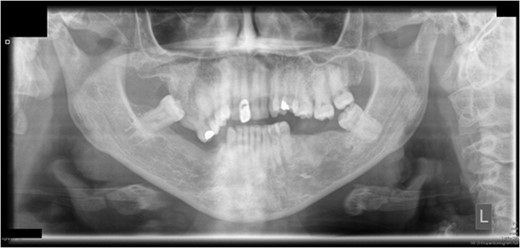

Preoperative orthopantomograph showing expansion of the right maxillary tuberosity.

The operation planned was a Le Fort I osteotomy with a right posterior segment osteotomy, which would set back the upper incisors by 6 mm, impact the upper left second molar by 4 mm and impact the posterior segment from the upper right first premolar (by 5 mm) to the upper right first molar (by 12 mm). No forward movement of the maxilla was planned. The segmental osteotomy was performed following down fracture of the maxilla and the final occlusion was aligned to a full coverage occlusal splint. The right descending palatal artery was sacrificed.